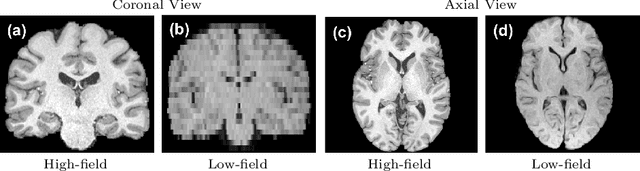

Abstract:1.5T or 3T scanners are the current standard for clinical MRI, but low-field (<1T) scanners are still common in many lower- and middle-income countries for reasons of cost and robustness to power failures. Compared to modern high-field scanners, low-field scanners provide images with lower signal-to-noise ratio at equivalent resolution, leaving practitioners to compensate by using large slice thickness and incomplete spatial coverage. Furthermore, the contrast between different types of brain tissue may be substantially reduced even at equal signal-to-noise ratio, which limits diagnostic value. Recently the paradigm of Image Quality Transfer has been applied to enhance 0.36T structural images aiming to approximate the resolution, spatial coverage, and contrast of typical 1.5T or 3T images. A variant of the neural network U-Net was trained using low-field images simulated from the publicly available 3T Human Connectome Project dataset. Here we present qualitative results from real and simulated clinical low-field brain images showing the potential value of IQT to enhance the clinical utility of readily accessible low-field MRIs in the management of epilepsy.

Abstract:MR images scanned at low magnetic field ($<1$T) have lower resolution in the slice direction and lower contrast, due to a relatively small signal-to-noise ratio (SNR) than those from high field (typically 1.5T and 3T). We adapt the recent idea of Image Quality Transfer (IQT) to enhance very low-field structural images aiming to estimate the resolution, spatial coverage, and contrast of high-field images. Analogous to many learning-based image enhancement techniques, IQT generates training data from high-field scans alone by simulating low-field images through a pre-defined decimation model. However, the ground truth decimation model is not well-known in practice, and lack of its specification can bias the trained model, aggravating performance on the real low-field scans. In this paper we propose a probabilistic decimation simulator to improve robustness of model training. It is used to generate and augment various low-field images whose parameters are random variables and sampled from an empirical distribution related to tissue-specific SNR on a 0.36T scanner. The probabilistic decimation simulator is model-agnostic, that is, it can be used with any super-resolution networks. Furthermore we propose a variant of U-Net architecture to improve its learning performance. We show promising qualitative results from clinical low-field images confirming the strong efficacy of IQT in an important new application area: epilepsy diagnosis in sub-Saharan Africa where only low-field scanners are normally available.